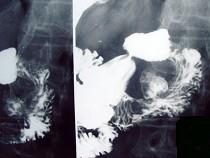

问题 男,55岁,中上腹隐痛多年,剑突下压痛,影像检查如图,最可能的诊断是 ( )

选项 A、十二指肠重复畸形 B、十二指肠穿孔 C、十二指肠憩室 D、十二指肠癌 E、十二肠溃疡

答案 C